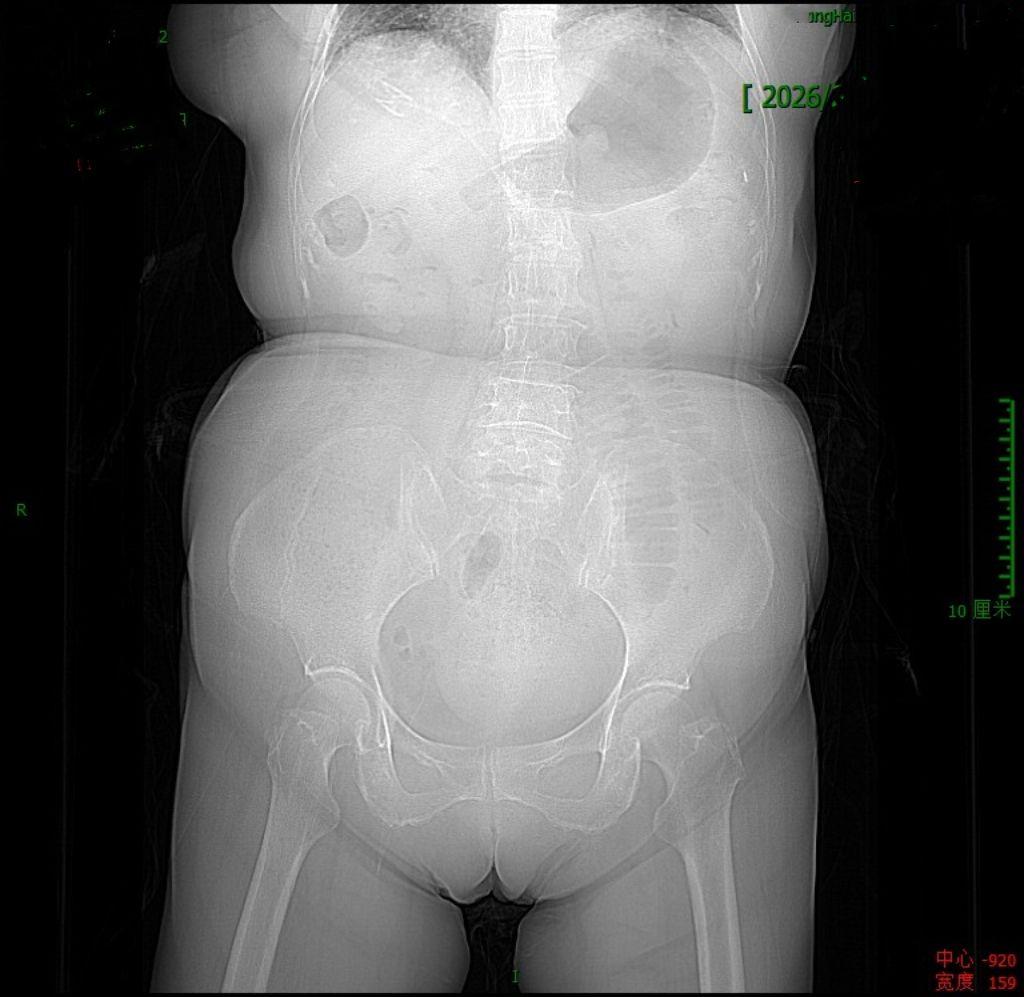

化疗后真的很容易发生肠梗阻

肿瘤化疗后,由于患者体能差,胃肠道蠕动变弱,长期卧床,确实很容易发生肠道梗阻。所以如果化疗后两三天大便不通畅,就得警惕了,早期干预,避免发生肠梗阻,或者其他更为严重的合并症。